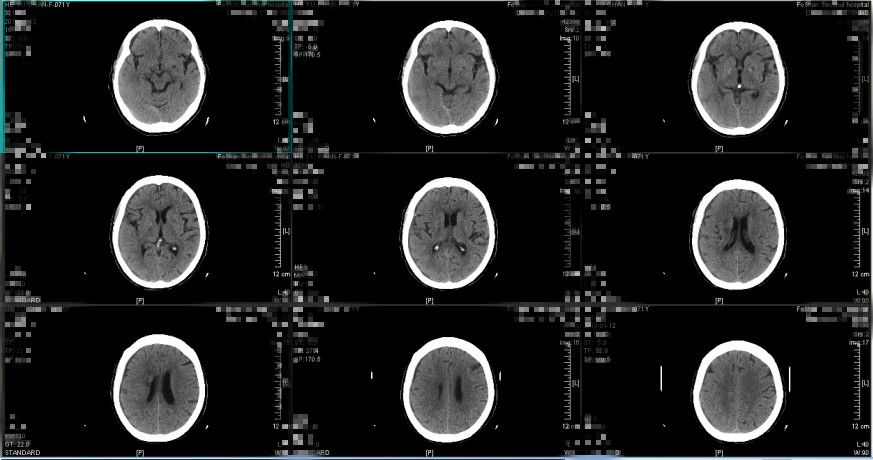

图1. 入院前急诊查头颅CT提示:1.右侧额颞顶部硬膜下血肿,中线略向左移位2.考虑少量蛛网膜下腔出血(2018-12-21 12:53)

患者入院时受伤程度轻,无昏迷,GCS评分15分,提示脑挫伤轻微;入院时头颅CT提示沿硬膜下间隙分布的窄弧带样高密度影,呈断线样高低密度混杂影,中线结构向左偏移约0.5cm,最大血肿厚度约0.8cm,基底池无受压,血肿多位于侧裂附近额顶部,且患者为老年女性,脑萎缩提供了一定的代偿空间,综合考虑此病例为“早期快速自然消散”的特殊类型急性创伤性硬膜下血肿。详细与患者及其家属讲解病情后,采取保守治疗观察方案,密切观察生命体征变化,保持呼吸道通畅,密切观察神经系统体征,给予止血、维持水电解质平衡、控制血压等对症支持处理,未予脱水药物处理,拟伤后12小时再次复查头颅CT检查。

图4. 伤后约10小时复查头颅CT提示:硬膜下血肿较前减少消散,以低密度血肿减少为主,中线结构偏移程度减轻。(2018-12-21 20:16)

患者入院后仍保持清醒状态,头痛等症状无继续加重,根据复查头颅CT检查提示硬膜下血肿较前减少,最大血肿厚度约0.5cm,中线向左偏移约0.3cm,提示此病例为“早期快速自然消散”的特殊类型急性创伤性硬膜下血肿,继续予保守治疗观察。

图5. 入院后第二天复查头颅CT提示:硬膜下血肿继续较前减少消散,中线结构大致居中。(2018-12-22 14:53:08)

图6. 入院后第九天复查头颅CT提示:亚急性硬膜下血肿形成,血肿量较前增多。(2018-12-29 15:36:23)